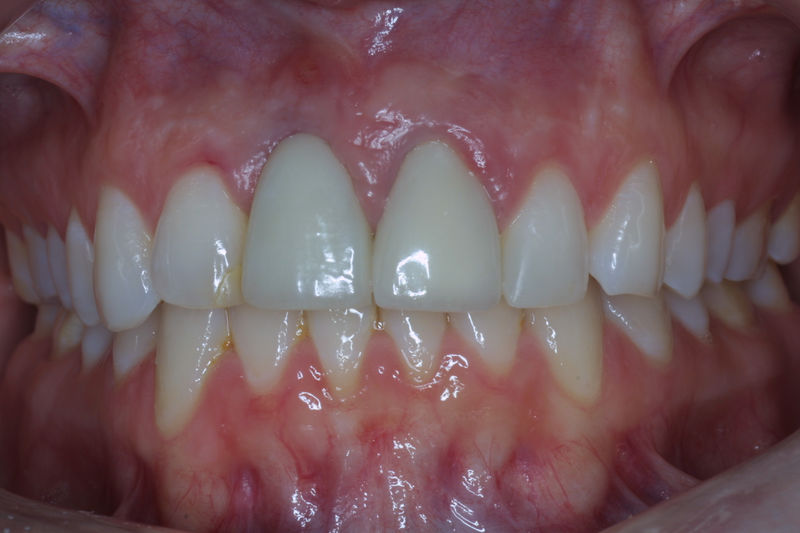

Amplia gama de tratamientos para mejorar la apariencia de la sonrisa, corrigiendo el color, la forma, el tamaño, la alineación y la posición de los dientes. Los procedimientos más comunes y solicitados incluyen el blanqueamiento dental, las carillas y coronas, así como las resinas.

Son restauraciones que cubren toda la cara frontal del diente, generalmente empleadas en el sector anterior y cuya finalidad es primariamente estética.

Restauraciones fabricadas en el laboratorio con materiales estéticos, los cuales cubren de manera total dientes anteriores y posteriores. Se utilizan primariamente para restaurar dientes con caries, fracturas y/o defectos amplios, así como soportes de puentes. Para poder enviar el caso al laboratorio se toman impresiones utilizando materiales de impresión o técnicas modernas digitales.